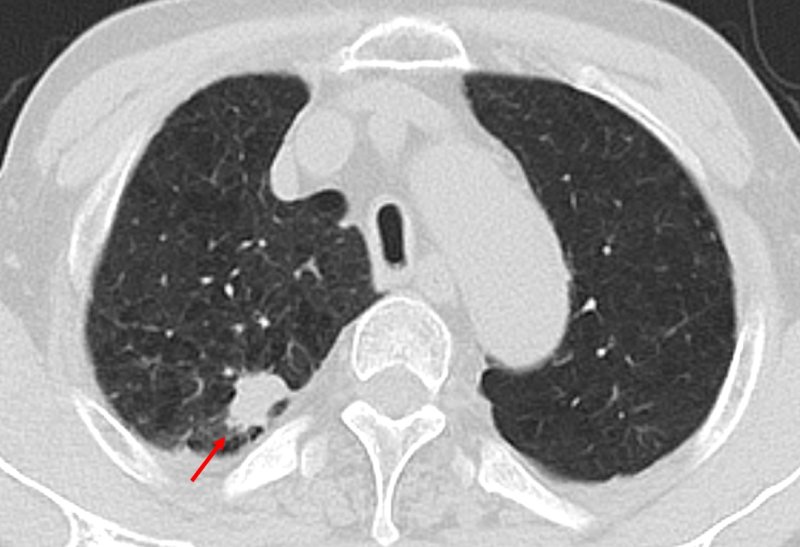

[서울=뉴시스] 저선량 흉부 CT 검사에서 폐결절 확인 사진. (사진= 한림대동탄성심병원 제공)

분석 결과 전체 대상자의 절반 이상인 55.8%(786명)에게서 폐결절이 발견됐고, 이 중 12.7%(179명)는 양성 폐결절이었다. 양성 폐결절은 암(악성)이 아니지만 극히 일부는 폐암으로 진단되거나 크기가 증가하며 폐암으로 진행될 수 있어 추적관찰이 요구된다. 양성 폐결절 환자에게 적절한 추적관찰을 진행한 결과 2.2%(31명)가 폐암으로 진단됐다.